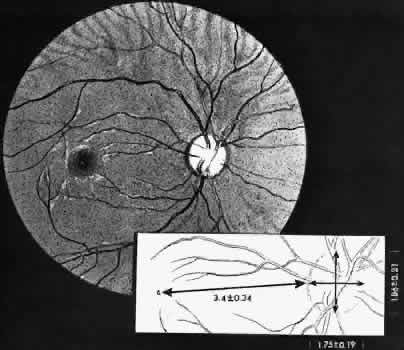

retinal layer; it rarely requires treatment.  Fig. 19. Clinical appearance of typical degenerative retinoschisis: diagram of involved

area and ocular fundus photographs showing optic disc, macula, and

posterior portion of schisis. Within the schisis and adjacent to

the margin is coarse stippling related to broken retinal pillars. Fig. 19. Clinical appearance of typical degenerative retinoschisis: diagram of involved

area and ocular fundus photographs showing optic disc, macula, and

posterior portion of schisis. Within the schisis and adjacent to

the margin is coarse stippling related to broken retinal pillars.

|